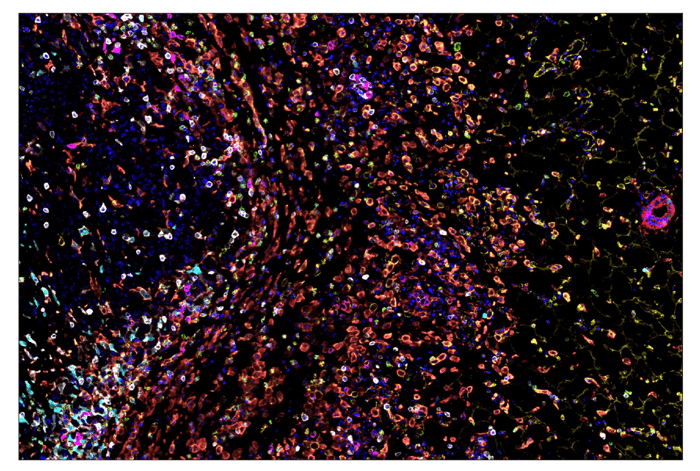

SignalStar® multiplex immunohistochemical analysis of paraffin-embedded GL261 syngeneic tumor using CD11b/ITGAM (E4K8C) & CO-0083-488 SignalStar Oligo-Antibody Pair #39172 (green), CD36 (E8B7S) & CO-0089-594 SignalStar Oligo-Antibody Pair #23418 (yellow), Pan-Keratin (Type I) (E6S1S) & CO-0072-647 SignalStar Oligo-Antibody Pair #77030 (red), IL-2Rα/CD25 (E9W2J) & CO-0074-750 SignalStar Oligo-Antibody Pair #71915 (magenta), CD8 alpha (D4W2Z) & CO-0040-488 SignalStar Oligo-Antibody Pair #17707 (white), Arginase-1 (D4E3M) & CO-0075-594 SignalStar Oligo-Antibody Pair #66757 (cyan), F4/80 (D2S9R) & CO-0042-750 SignalStar Oligo-Antibody Pair #51924 (orange), and DAPI #4083 (blue). All fluorophores have been assigned a pseudocolor, as indicated. Staining was performed on the BOND RX autostainer by Leica Biosystems.